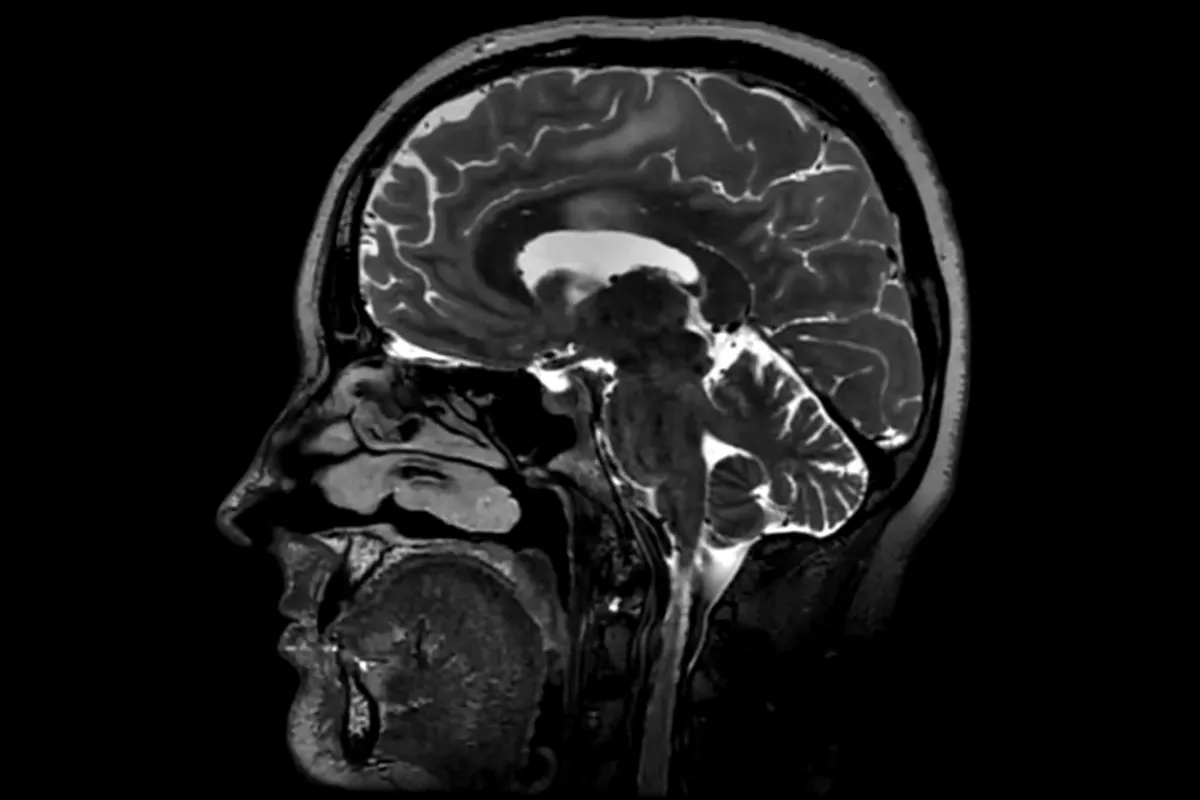

Este hallazgo puede proporcionar un contexto importante sobre las áreas en las que los cerebros podrían ser mejores o más vulnerables según la etapa de vida. (LYagovy/Getty Images)

Este hallazgo puede proporcionar un contexto importante sobre las áreas en las que los cerebros podrían ser mejores o más vulnerables según la etapa de vida.